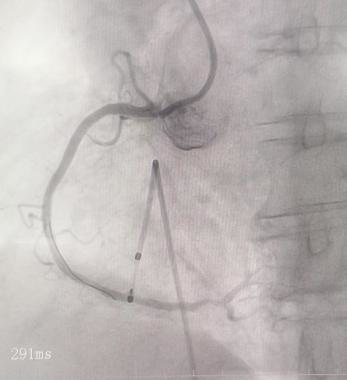

内一科学科带头人李绍波主任在介入室为患者实施了临时起搏器置入术,并同步进行冠脉造影。结果显示,患者冠状动脉存在多处严重狭窄。李绍波主任随即进行药物球囊扩张和支架植入,成功疏通血管,恢复血流。术后,患者生命体征平稳,心率逐渐恢复正常,心电图也未见异常。

术前 术后